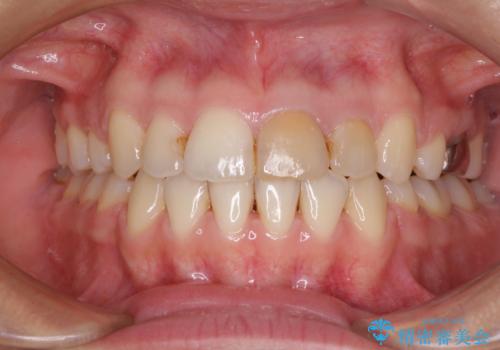

- 上下の前歯が突出しており、口が閉じにくいとのことで来院された患者様です。

上下前歯が著しく前突している状態であったので、上下左右の第1小臼歯4本を抜歯し、ワイヤー装置にて矯正治療を行うこととしました。

舌の突出癖があり、前歯の移動量も多くなるため、治療期間は長くなると予想されましたが、13ヶ月という予定の半分程度の期間で終えることができました。